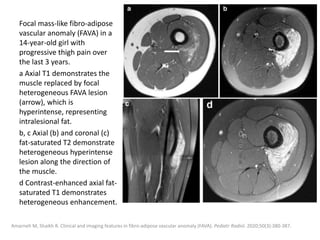

can then be treated with the sclerosant.

Müller-Wille R, Wildgruber M, Sadick M, Wohlgemuth WA. Vascular Anomalies (Part II): Interventional Therapy of Peripheral Vascular

Malformations [published online ahead of print, 2018 Feb 7]. Gefäßanomalien (Teil II): Interventionelle Therapie von peripheren

Gefäßmalformationen [published online ahead of print, 2018 Feb 7]. Rofo. 2018;10.1055/s-0044-101266.

Post-procedural care

Strict postoperative observation of the upper

airway is recommended after treatment of

patients with large cervical LMs.